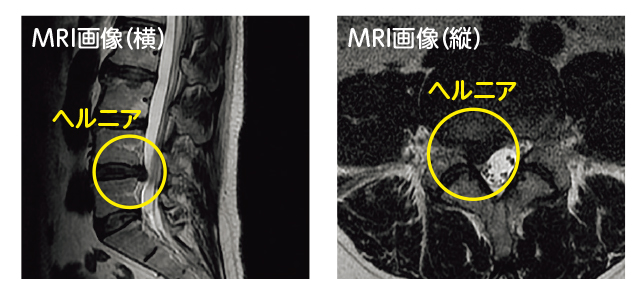

問診と身体所見で身体の状態を確認し画像検査で診断をします。問診で重い物を持ってからとか身体を捻ってからとか、咳やくしゃみをしてから症状が出たなどのきっかけを聞くことは診断をする上で重要です。画像診断は特にMRIが重要で椎間板の出っ張りを確認したり神経の圧迫を確認したりします。最近はMRミエログラフィーで神経根のみを描出して外側病変があるかどうかの診断にも役立てています。

椎間板ヘルニアの検査方法